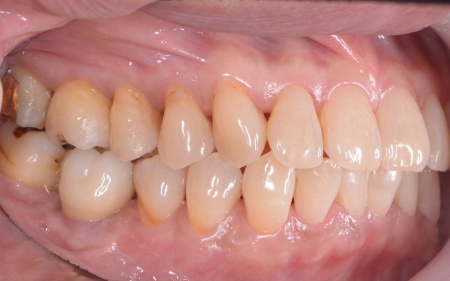

| カウンセリング | 拝見したところ、上下左右の奥歯計8本(第1大臼歯、第2大臼歯)に重度の歯周病が認められました。 歯周病は歯を支えている骨や歯ぐきに炎症が起こる病気です。進行すると歯がぐらついたり、噛む力が弱くなったりします。 さらに悪化すると歯を失う可能性が高くなるだけでなく、周囲の歯にも影響が広がることがあります。 特に下の奥歯2本(左右第1大臼歯)は歯を支えている骨が著しく減少して歯が大きく揺れており、治療して温存することは難しい状態でした。 また、左上の奥歯(第1大臼歯)は過去に詰め物で治療されていましたが、その下で虫歯が再発しています。 以上のことから、下左右の第1大臼歯は抜歯後に歯を補う治療、その他奥歯の治療、再発した虫歯の治療が必要と診断しました。 |

さらに虫歯が再発していた左上奥歯については、虫歯をしっかりと取り除いたうえで被せ物による修復治療を提案しました。 それぞれのメリット・デメリットを丁寧に説明したところ、治療計画に同意いただきました。 まず、歯周基本治療から開始しました。 下左右の第1大臼歯を抜歯し、その部位にインプラントを埋め込む手術を行いました。同時に、インプラントの隣にある下の第2大臼歯に対して歯周組織再生療法を施しています。 また、左上の奥歯は虫歯を取り除いたあと、歯の形を整えて型取りを行い、最終的にジルコニアクラウンを装着しています。 段階的に治療を進め、すべての治療を終了しました。 |